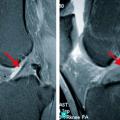

Fracture du pilon tibial

LESIONS PERI-ARTICULAIRES

LESIONS LIGAMENTAIRES